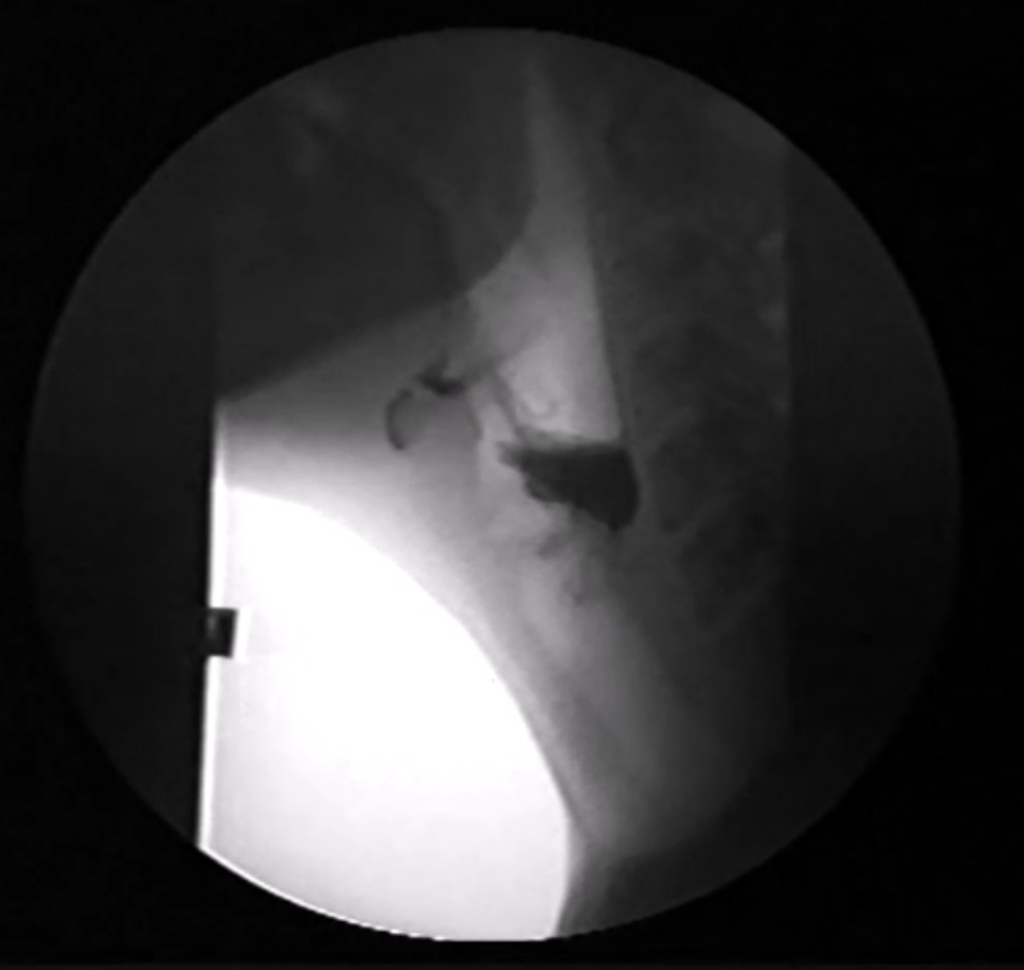

Upper esophageal sphincter (UES) dysfunction, defined as inappropriate opening or failed relaxation of the UES during swallowing, is a common cause of dysphagia. This research project consists of two parts: I- a systematic review of the literature to assess UES intervention trends and their impact on patient outcomes. II- Development of a multi-site study to explore the comparative effectiveness of two common intervention types.

Intervention for Upper Esophageal Sphincter Dysfunction